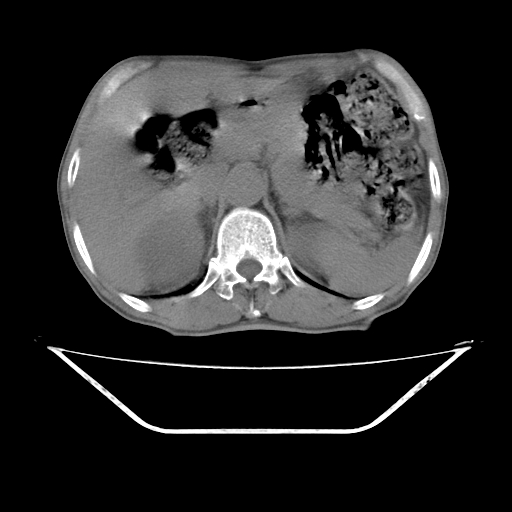

增强

考虑右肾盂癌,肾动脉受侵,右肾功能减退,右肾盂输尿管积水,管壁增厚,考虑种植转移,应该把下面扫完的

支持右侧肾盂癌伴肾静脉瘤栓形成可能性大,右肾结石.肝右叶后段低密度影,不除外转移.

右肾囊实性占位,支持肾癌,窗宽窗位不是很理想

右肾盂旁ca并肾静脉瘤栓形成/肾功能降低。

右肾结石。

右肾盂癌,肾动脉受侵,右肾盂输尿管积水,管壁增厚,考虑种植转移

右肾盂移行细胞癌并右输尿管中段转移.肾积水.

支持 右侧肾盂癌伴肾静脉瘤栓形成可能性大,右肾结石;肝右叶后段低密度影,不除外转移。

1.右侧肾盂癌伴肾盂积水。

2.肾脏功能减退,原因有:(1)肾动脉受侵。(2)肾静脉受侵(3)肾积水,等。本例,肾动脉显影较好,但受压明显;肾静脉无明显显示,受压或静脉癌栓,下腔静脉腔内未见明显充盈缺损。

3.右侧上段输尿管扩张,原因:(1)积水所致;(2)种植。